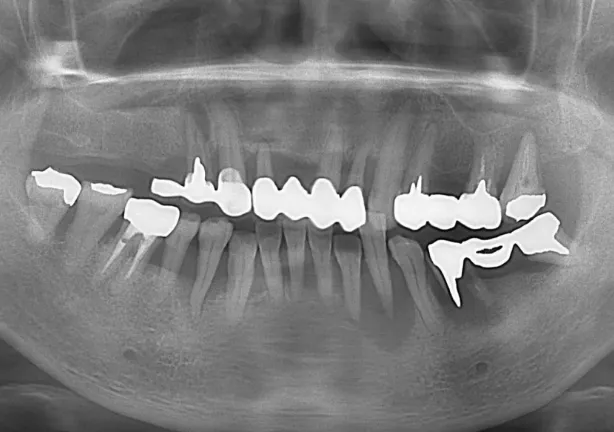

Before